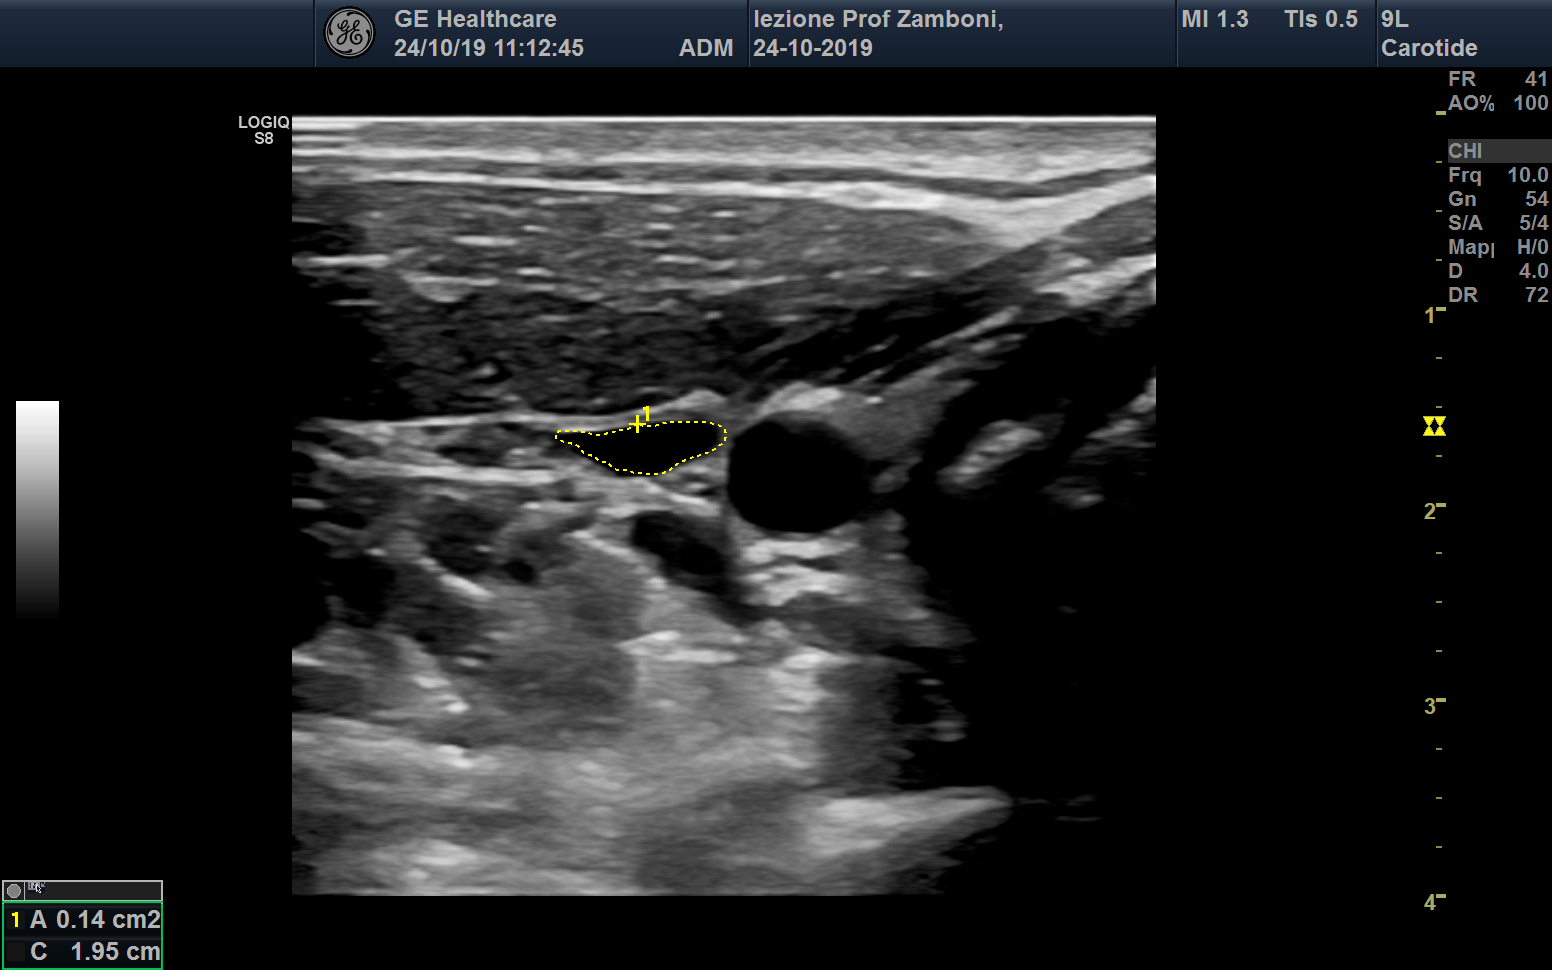

Area Giugulare Seduto

JPEG image icon Area Giugulare Seduto.jpg — JPEG image, 425 kB (435357 bytes)